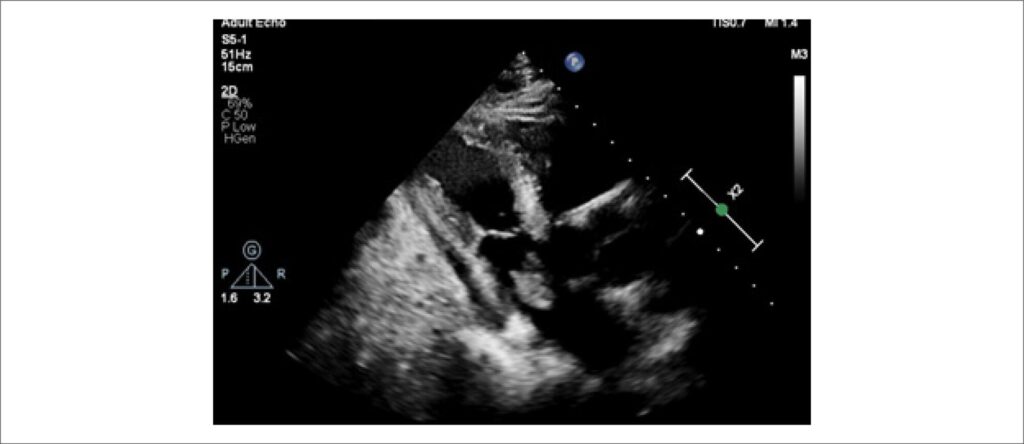

Mixoma Atrial Como Causa Rara de Acidente Vascular Cerebral: Relato de Caso

O mixoma atrial (MA) é o tumor benigno primário que mais comumente afeta o coração. Tem prevalência rara, estimada em 0,03% na população geral, devendo levar a intervenção cirúrgica assim que diagnosticado por apresentar risco aumentado de complicações cardíacas, como obstruções intracardíacas ou embolizações sistêmicas.

Mixomas cardíacos são observados no átrio esquerdo em >75% dos casos, predominantemente fixados com um pedúnculo à fossa oval (>90%). No entanto, podem ser vistos em outros locais (ventrículo esquerdo, átrio direito e muito raramente o ventrículo direito).